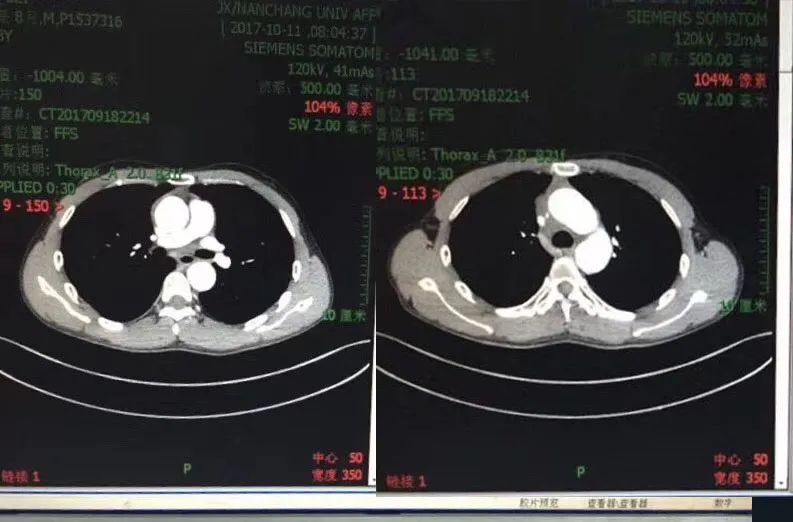

“来就诊的时候已经是肝癌晚期了,并且已经转移到了肺部,就诊的时候出现了呼吸困难的症状。”南大一附院肿瘤医学中心主任熊建萍告诉记者,患者来就诊时的病情非常严重,肿瘤已经压迫到了患者的气管,当时气管仅留下一条缝,情况比较危急,医院马上通过免疫治疗等各种方式进行治疗。

“经过我们治疗,小伙子复查后病灶明显缩小。前两个月来复查,肺部病灶几乎全部消失了,疾病控制时间已经达到了3年。”据了解,患者是一名卡车司机,同时还是3个孩子的父亲,家里的生计全靠他一个人。通过治疗后,恢复了正常生活,患者现在还能开着卡车在全国跑。